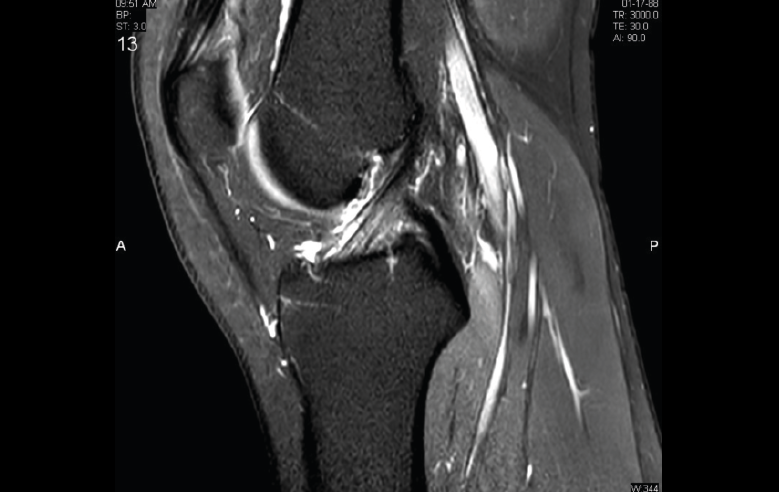

4. Lesiones isquémicas

4.1. Necrosis avascular (NAV)

En la NAV (aséptica, isquémica u osteonecrosis), hay una pérdida del flujo de sangre en el tejido óseo que hace que el hueso muera.

Se produce por un trastorno de la irrigación sanguínea o por lesiones celulares en el hueso y en la médula ósea.

Puede observarse en la RM la disminución de la intensidad de la lesión mucho antes de que se aprecie con otras pruebas diagnósticas (Figura 51).

Figura 51. Corte de secuencia T2 Fat-Sat coronal: lesión osteocondral con necrosis avascular del fragmento óseo.